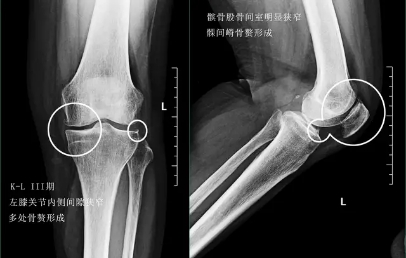

前面已经说到骨关节炎会导致骨赘的形成以及关节间隙的狭窄,所以我们依靠膝关节x片子来初步判断骨关节炎的病情,通常我们采用K_L分期判断病情。

三期患者:3期的患者不仅有了骨赘大量形成,而且关节间隙已经开始发生了明显的狭窄,患者的症状会越来越严重,很多会表现出来蹲起的疼痛,甚至有的患者不能长时间的行走,否则次日关节就会有明显的肿胀,有的患者在屈伸关节的过程当中会听到响声,类似于冬天我们用脚踩雪的那种响声。

在此阶段我们通常仍然会采取关节内注射的办法以及一些保守治疗的办法,缓解患者的痛苦。患者也可以口服仙灵骨葆这一类的中成药。